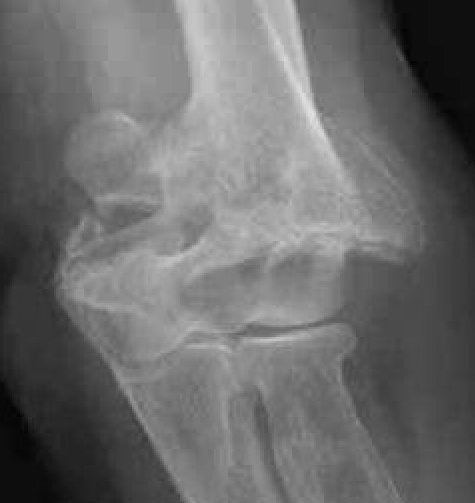

OTA / AO Classification

Type A: Extra-articular fracture

Type B: Partial articular fractures

Lateral condyle Medial condyle

Type C: Complete articular fractures

CT scan